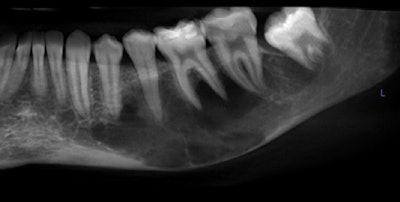

Figure 1: Cropped, reformatted panoramic film of the left mandible.Images courtesy of Dr. Juan F. Yepes.

- A cropped, reformatted pano film of the left mandible

There is a large hypodense lesion (radiolucent), well defined and corticated, extending from the mesial aspect of tooth #17 to the periapical area of tooth #22. The lesion goes from the inferior cortex of the mandible to the alveolar ridge of teeth #18 and #19, the middle third of the root of tooth #20, and the apical third of the root of tooth #21. There is evidence of significant expansion in the coronal and axial projections. No calcifications are observed within the lesion. No periosteal reaction is observed (lingual or buccal). There is no radiographic evidence of perforation of the buccal or lingual walls of the lesion.

There is no radiographic evidence of root resorption or teeth displacement associated with the lesion. No gross caries is present in the teeth involved in the lesion. The inferior alveolar canal is well visualized and displaced buccally-apically by the lesion.

Unicystic ameloblastomas are benign, slow-growing, and locally aggressive tumors. They are a rare variant of ameloblastomas that usually occur in younger populations. The majority of cases are found in the posterior mandible. The lesion is often asymptomatic, although a large lesion can be symptomatic and may cause some swelling of the mandible.

From the radiographic perspective, unicystic ameloblastomas show expansive unilocular radiolucency with well-defined and well-corticated borders. Root resorption is often present with minimal displacement. The majority of cases are associated with an impacted or unerupted tooth. The differential diagnosis includes dentigerous cyst and keratocystic odontogenic tumor.